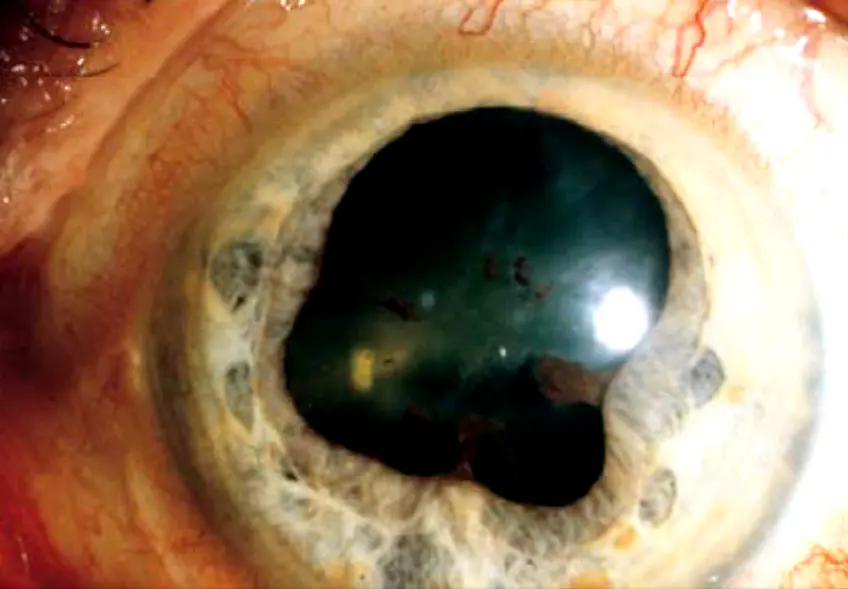

Posterior synechiae Y

Adhesion ( ) the iris and ant lens capsule